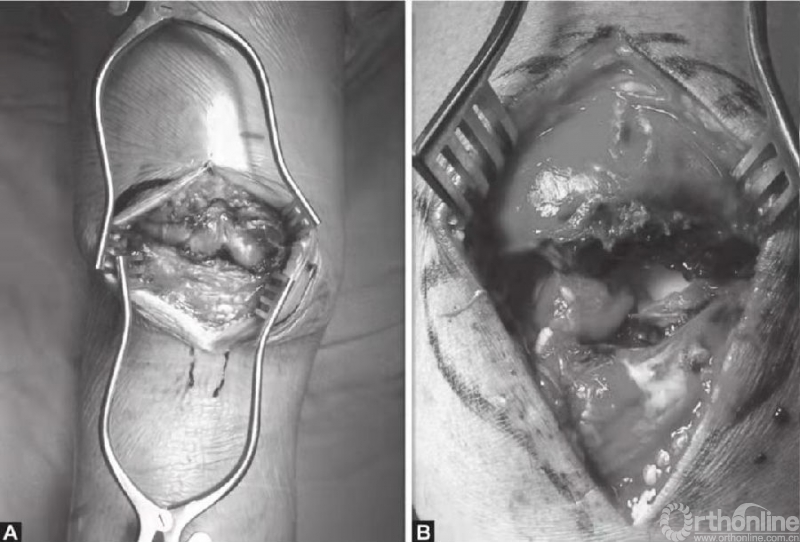

深层显露切口与皮肤切口方向一致。锐性分离深层筋膜,并牵开皮肤组织,进一步切开髌骨囊并清除血肿后骨折端即可显露(图4A和B)。此时,可见髌骨骨折以及撕裂的韧带。以生理盐水清洗血肿以及血凝块(图5)。撕裂的支持带可先辨识后,再进行修复。

图4 A和B切开髌骨关节囊,清除血肿后显露骨折块。图示髌骨横断型骨折,可见韧带撕裂